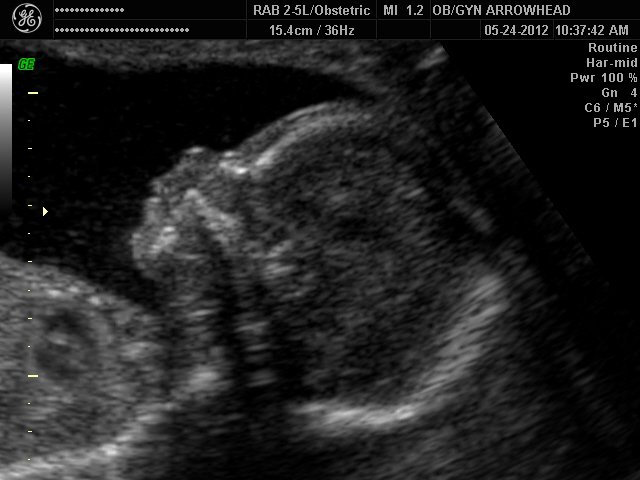

We offer complimentary 3D/4D Ultrasounds to all our OB patients around 30 weeks! The following photos are some examples of our work, shown with permission from our patients.